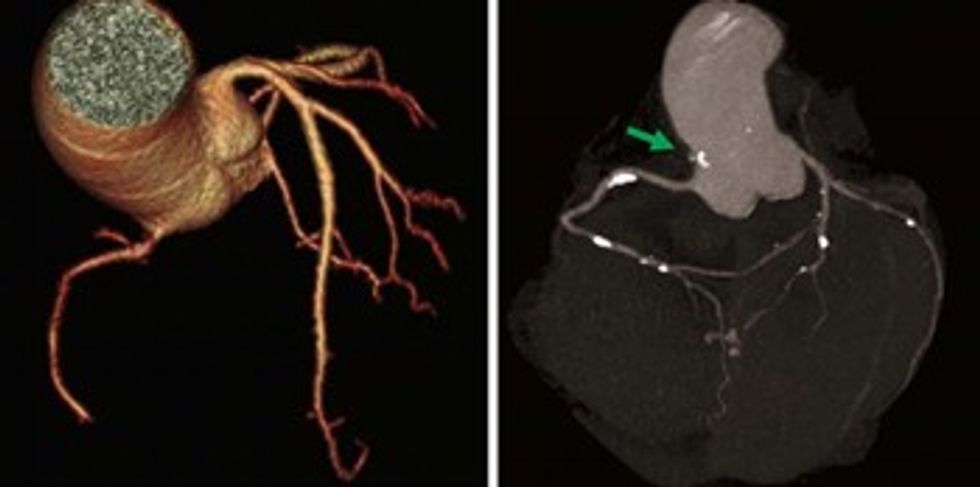

Enët e gjakut, arteriet dhe venat e çdo pjese të trupit mund të vlerësohen në tërë gjatësinë e tyre si dhe nga të katër anët.

Mund t’i analizojmë ndaras arteriet koronare dhe ta vlerësojmë patologjinë e tyre të mundshme.

Poashtu në masë të caktuar me koronarografi me tomografi të kompjuterizuar mund të analizohet edhe kalueshmëria e stenteve të vendosuara në arteriet koronare.

Me koronarografi me tomografi të kompjuterizuar mund të bëjmë vlerësimin e rrezikshmërisë nga sëmundjet aterosklerotike duke vlerësuar vlerat e kalciumit të deponuar në enët e gjakut (Calcium scoring) ose ngushtimet e vet arterieve koronare (stenozave).